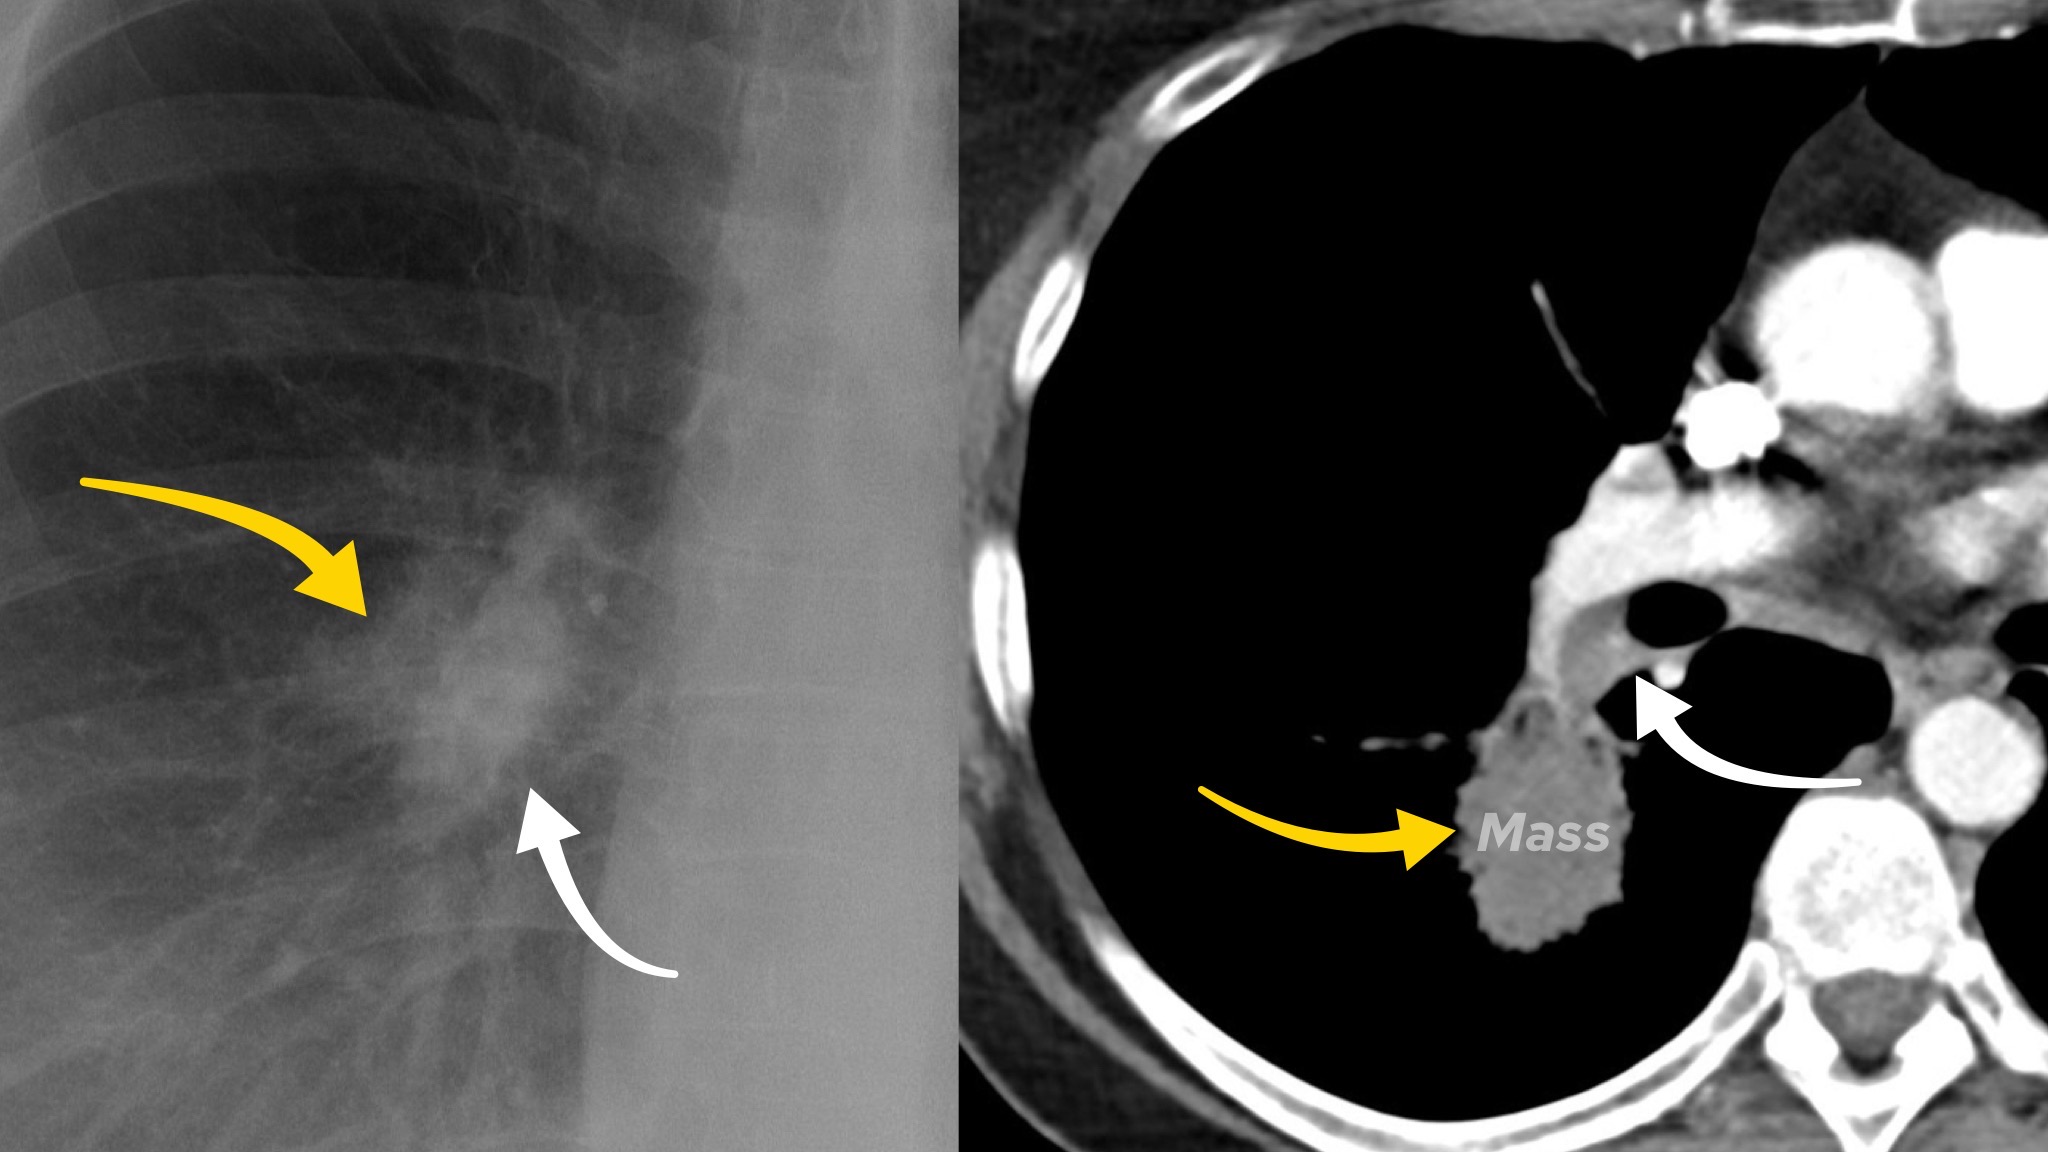

Case 1

A female in their 60s presents with unremitting cough on a background of weight loss. Have a look at the chest X-Ray below:

What is the most likely diagnosis? Choose from one of the following: